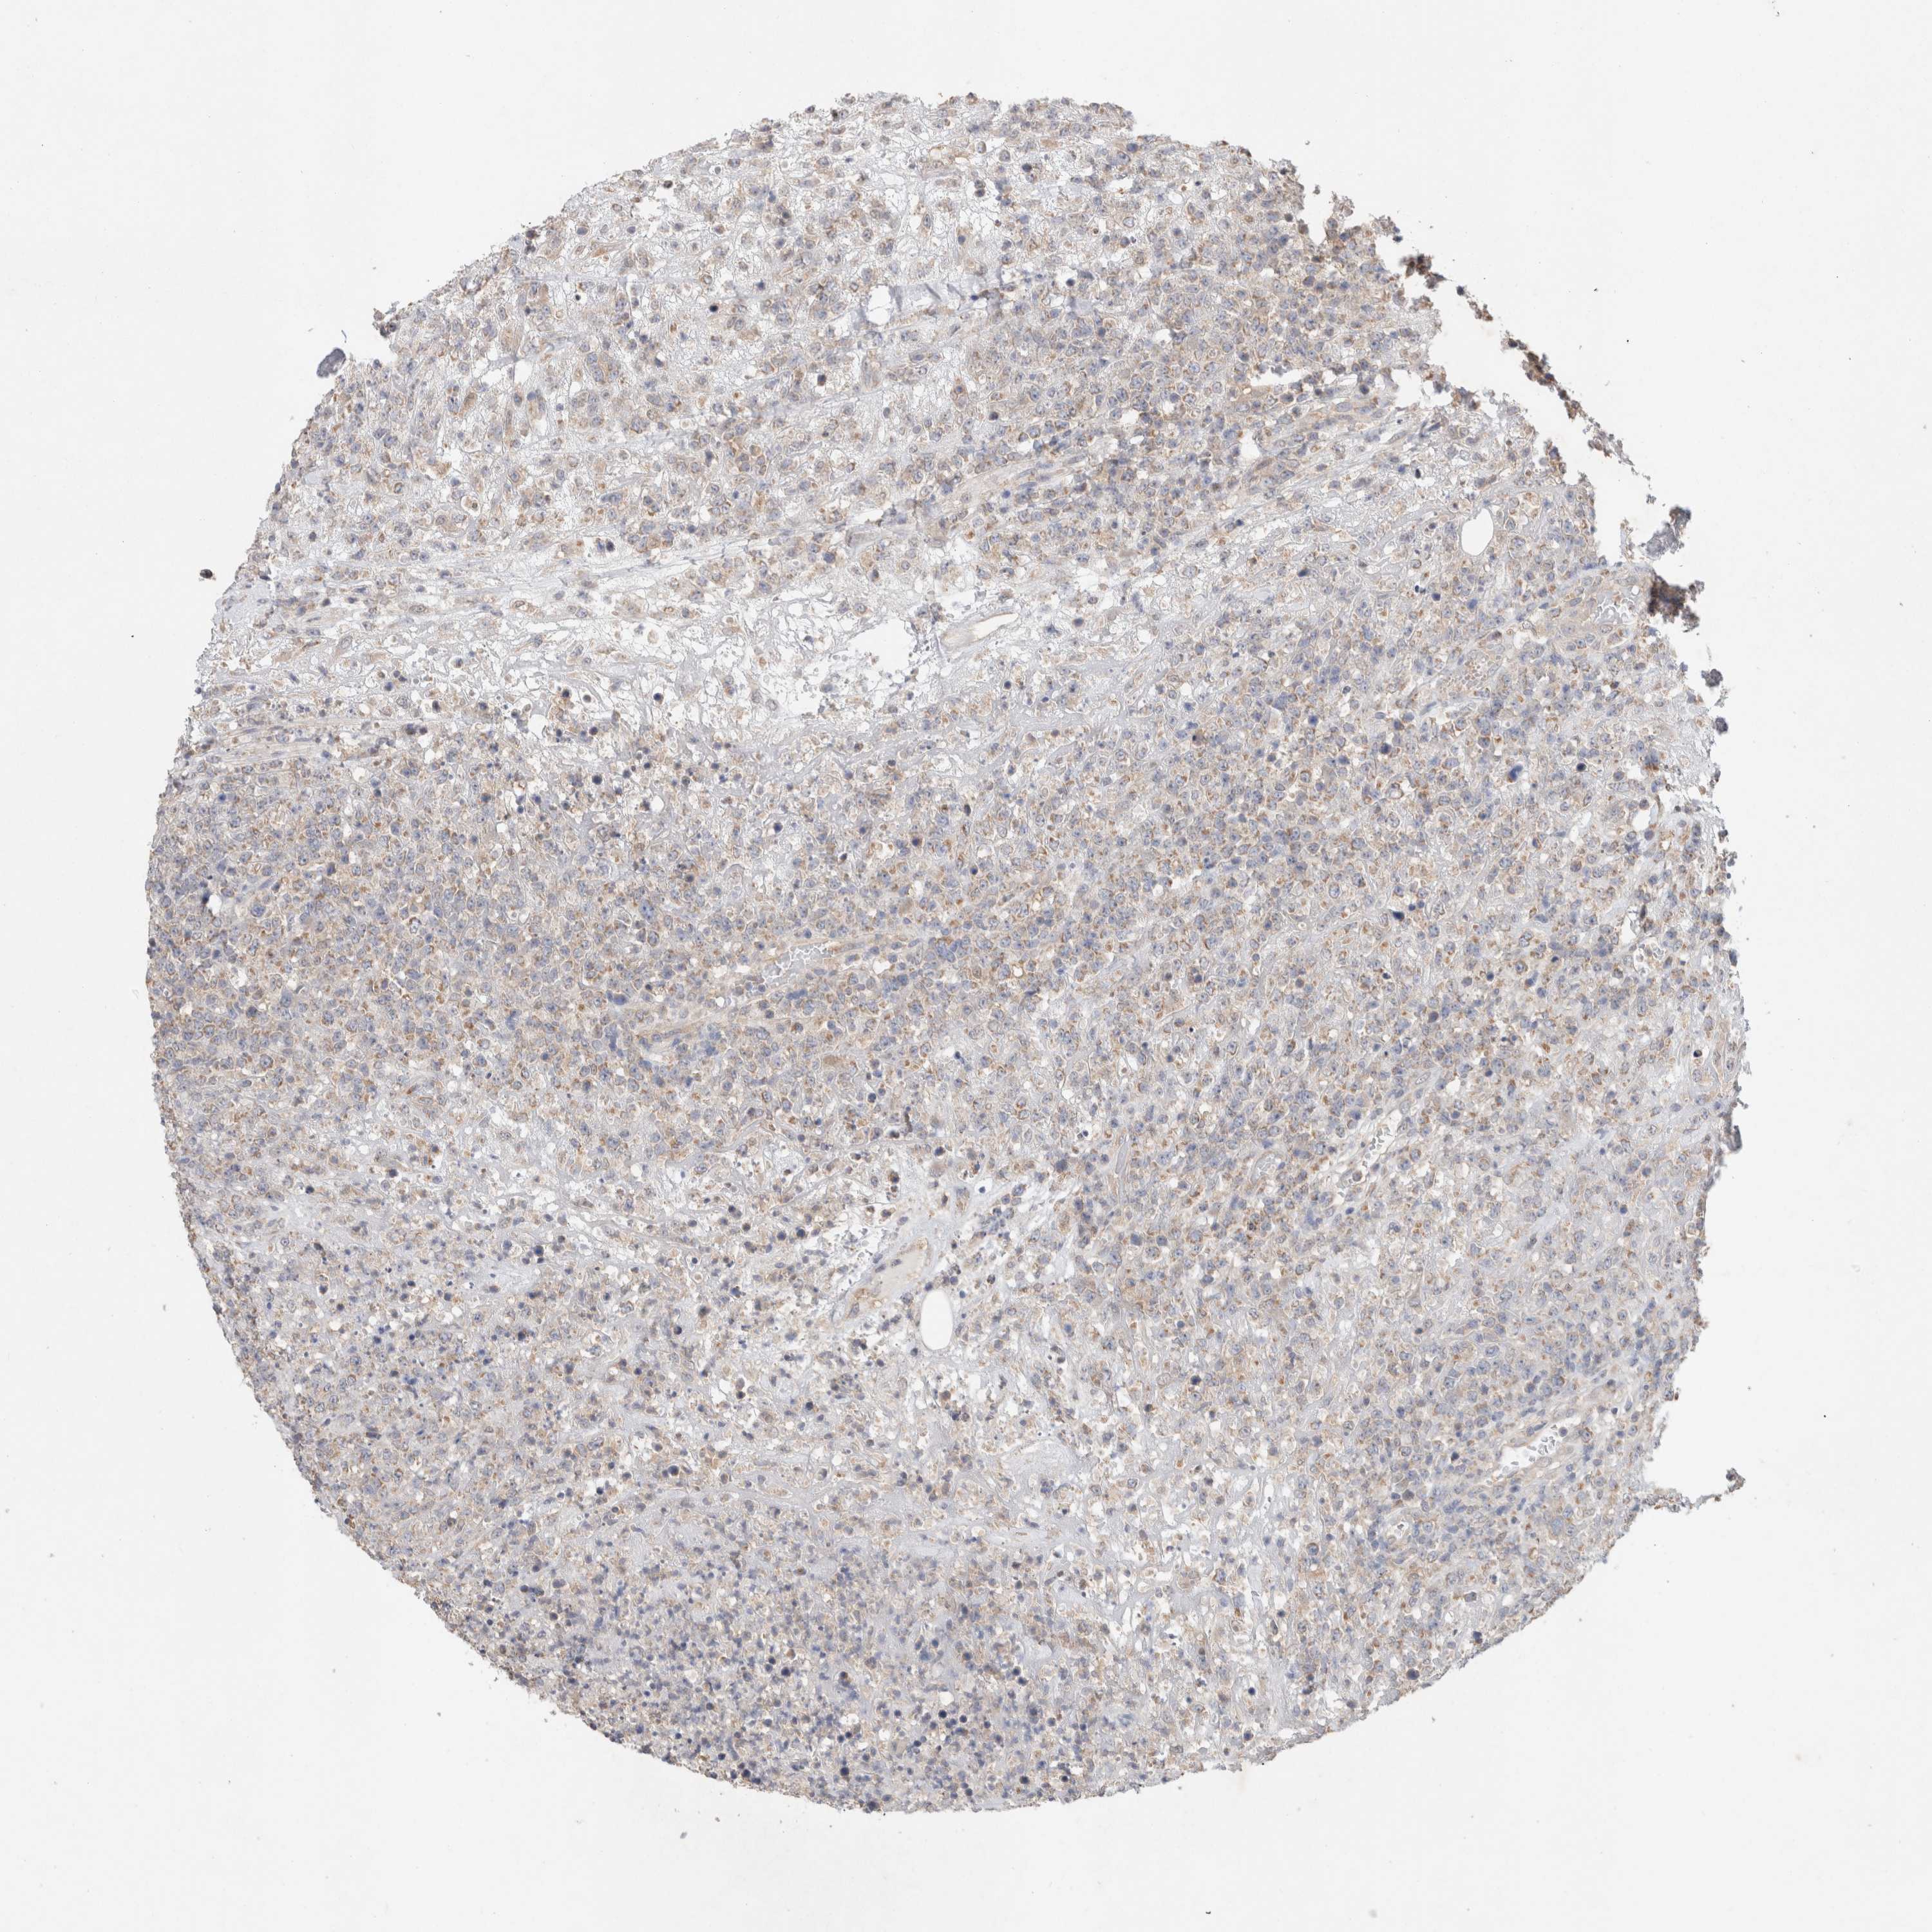

LYMPHOMA - Protein expressioni

A mouse-over function shows sample information and annotation data. Click on an image to view it in a full screen mode. Samples can be filtered based on level of antibody staining by selecting one or several of the following categories: high, medium, low and not detected. The assay and annotation is described here.

Antibody stainingi

Antibody staining in the annotated cell types in the current human tissue is reported as not detected, low, medium, or high, based on conventional immunohistochemistry profiling in selected tissues. This score is based on the combination of the staining intensity and fraction of stained cells.

Each image is clickable and will lead to virtual microscopy that enables deeper exploration of all samples and also displays staining intensity scores, fraction scores and subcellular localization as well as patient and tissue information for each sample.